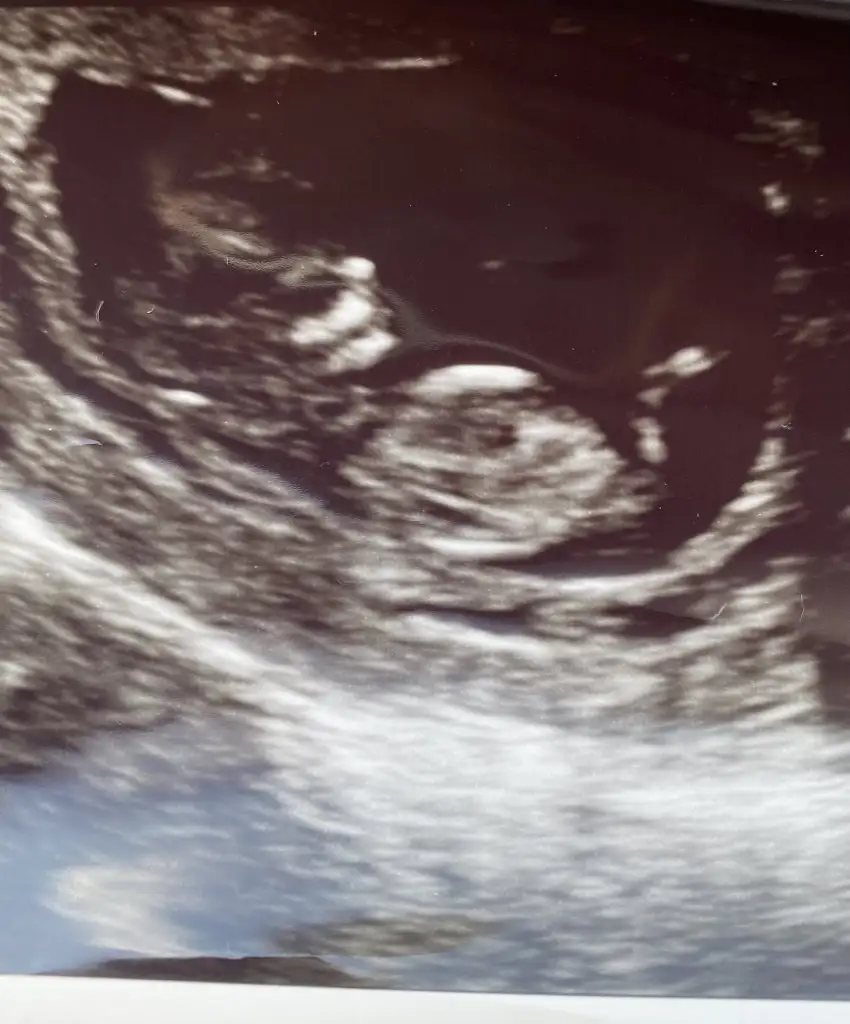

Başka resimlerde var nasıl olması gerekiyor o hafta ikili test filan derken elimde var doktor da kıza benziyor dedi amaNubu görünmüyor tipi kız gibi sanki![]()

Kiz görünüyorBunlarin dışında da var Bir daha bak buda olmaza diğerlerine bakiyim

Teşekkür ederim doktora gidince ekim sonu ne derse artık haber veririm..kıza benziyor demişti ilk resim için ikinci resmi doktor görmedi ikili testi yapan doktor gördü..cinsiyet farketmez ama merak işteKiz görünüyor